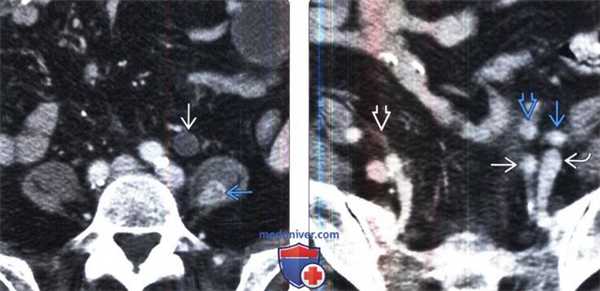

(Слева) КТ с контрастированием, аксиальная проекция: гидроуретер и контрастируемое метастатическое поражение в левой поясничной мышце.

(Справа) КТ с контрастированием, аксиальная проекция: у Этого же пациента визуализирован контрастируемый метастаз, блокирующий левый мочеточник. Видны левая общая подвздошная артерия и вена, а также левая семенная вена. Для сравнения показан нормальный правый мочеточник.